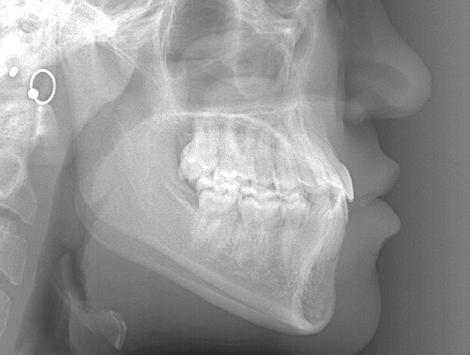

Cephalometric analysis confirmed a mild skeletal Class III relationship and normal vertical dimension. Both the maxillary and mandibular incisors were measurably mildly retroclined. The panoramic view was unremarkable. In fact, root length and bone level were excellent at the start of treatment.

The post-treatment cephalogram (Figure 8) shows the mild skeletal Class III relationship and mild mandibular incisor compensation, not surprising even with a successful orthodontic camouflage outcome. The only way to have avoided these cephalometric findings would have been to opt for and achieve a successful surgical result. This of course is never guaranteed. Most would agree that the camouflage option was a reasonable alternative to surgery in this patient.